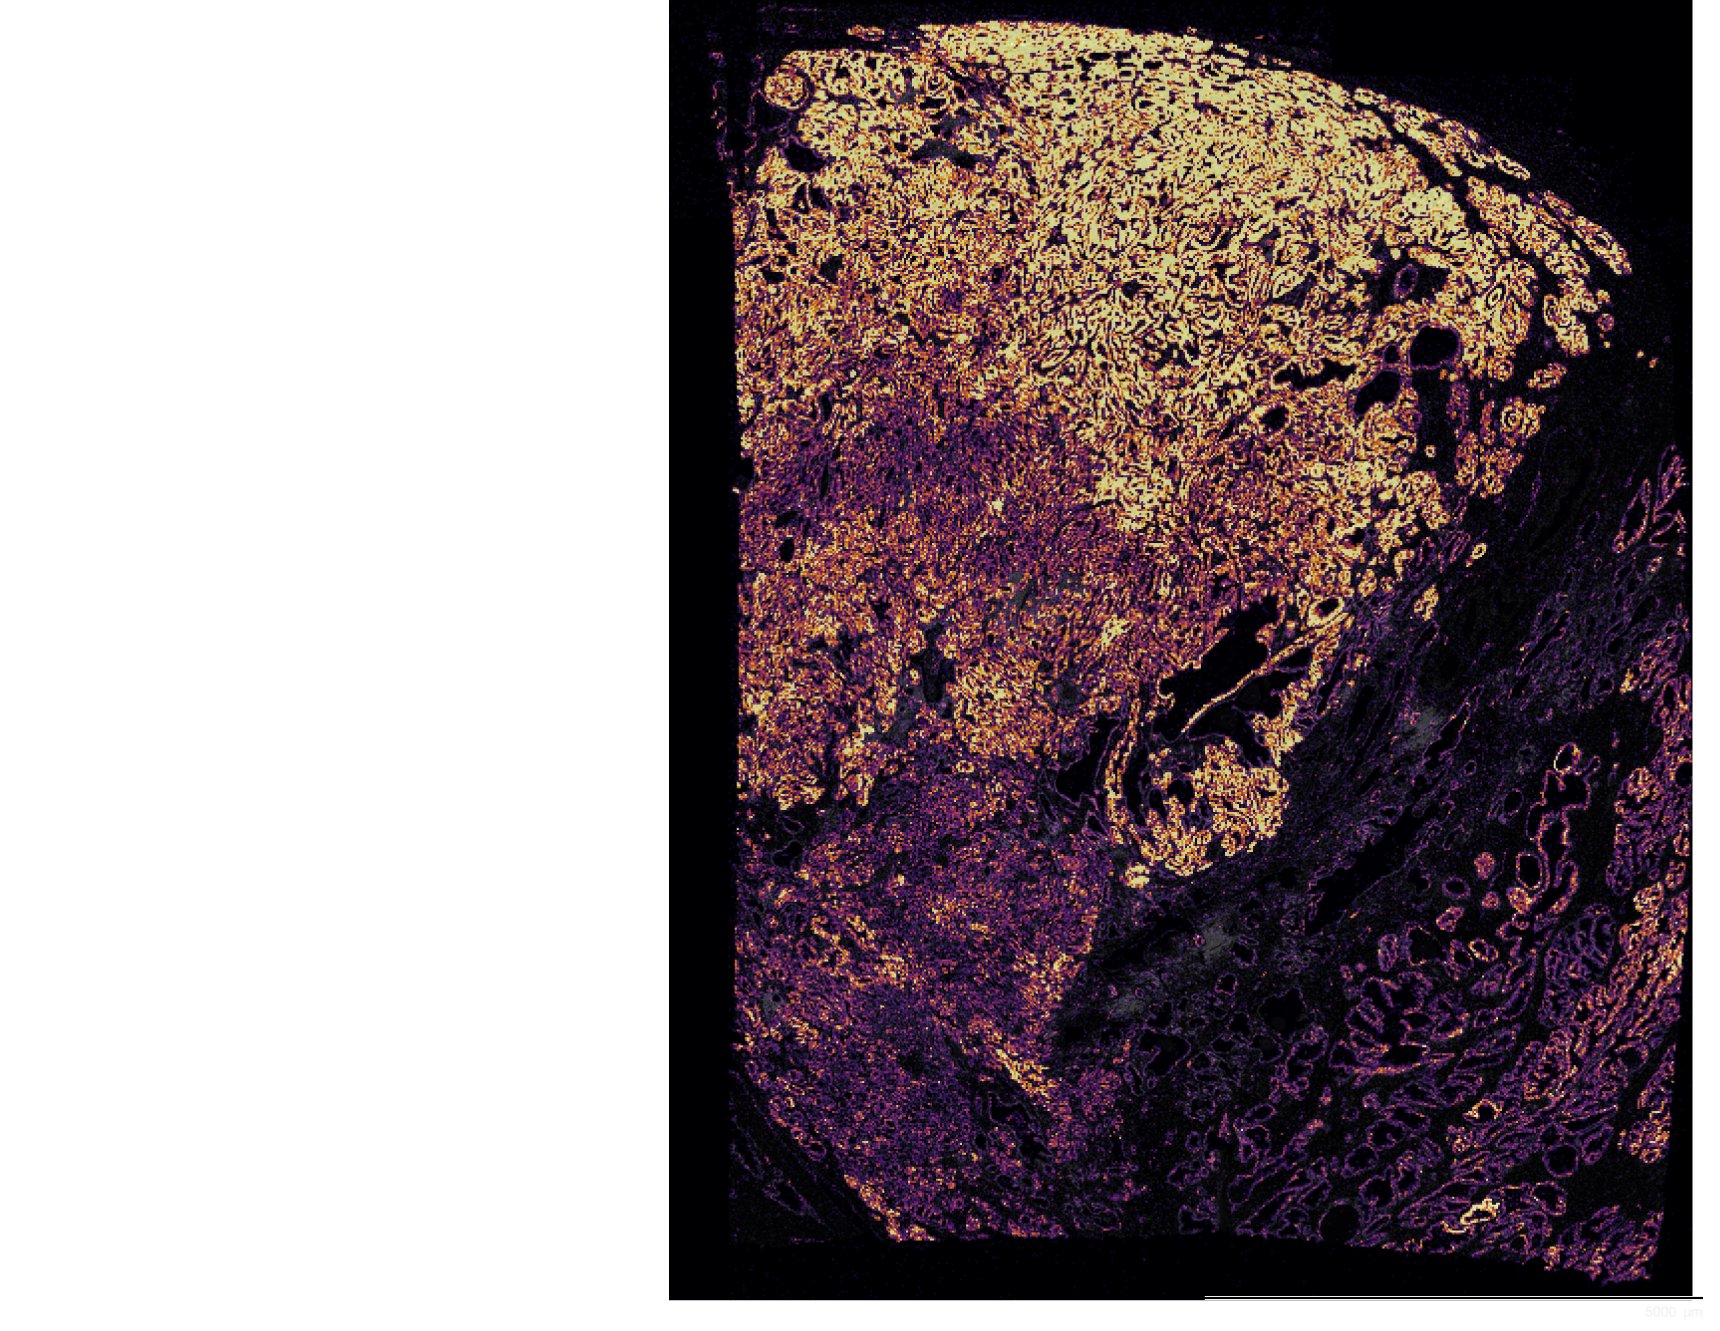

To study the heterogeneity and complexity of different kinds of disease, we apply 30+ antibodies on a single tissue section and use an automated imaging system to produce whole-tissue immunofluorescent images at single cell resolution.

The images below represent tumors from a variety of cancer types. Colors correspond to various proteins expressed by cells within the tumors, and illustrate the complex and diverse tumor microenvironment.